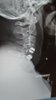

Been 3 weeks since the fusion of my spine. I'm not taking any pain meds, and if I do it's ibuprofen. I'm in some pain but I'm just not down with the narcotics. Been there before and it wasn't cool. I'm going in for a follow up on Wednesday. I'm gonna ask the doc if I can get on a treadmill or the stair stepper. I'm wondering if I can do an excersize that won't put any stress on my neck. I'm getting bored and restless. Sleep is tuff when you don't exert energy and are in pain...